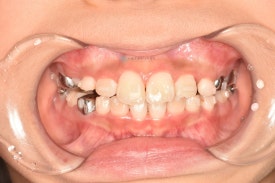

투명교정 10개월차입니다.

치료 후 - 유치 어금니들이 빠지고 영구치가 맹출하고 있습니다.송곳니가 나올 공간을 충분히 마련하며 확장하여 고른치열을 완성했습니다.

이대로 끝내도 좋겠지만 어린이투명교정치료의 18개월 기간이 아직 만료되지 않았습니다. 영구치 어금니 맹출을 조금 더 기다리다가 송곳니 어금니들이 맹출되면 그때 다시한번 장치를 만들어 앞니 디테일 마무리와 함께 새로 맹출하는 이들을 완벽하게 하고 마무리해하면 2차교정이 필요없을 것으로 생각됩니다.

치료 전 - 위아래 심한 공간 부족이 관찰됩니다.자세히 보면 아래 영구치 어금니의 충치도 치료하는 과정에서 깨끗하게 레진치료 해주었습니다. 교정하면서 충치검진이나 치료를 위해 다른 치과에 내원하지 않아도 된다는 점이 바쁜 우리 아이들에게는 큰 장점으로 다가오는 것 같습니다. 서울효앤주니어치과에서 교정체크 = 충치검진

자세히 보면 아래 영구치 어금니의 충치도 치료하는 과정에서 깨끗하게 레진치료 해주었습니다. 교정하면서 충치검진이나 치료를 위해 다른 치과에 내원하지 않아도 된다는 점이 바쁜 우리 아이들에게는 큰 장점으로 다가오는 것 같습니다. 서울효앤주니어치과에서 교정체크 = 충치검진